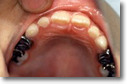

| 歯石除去 ![]() |